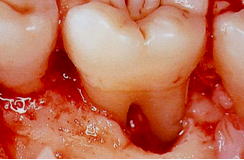

![]() |

7mm 以上のポケットの根分岐部は、完全な除去は困難 |